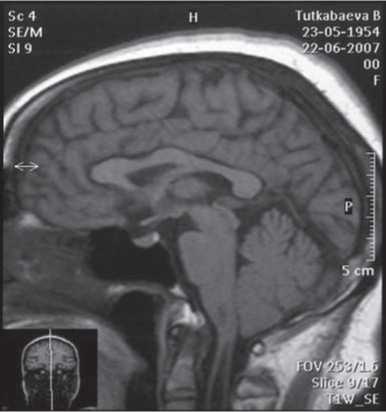

Эффективность лечения воспалительных заболеваний мозга представлена на примере лечения туберкулезного менингита (рис. 1), сирингомиелии (рис. 2, 3), перинатальной энцефалопатии и гидроцефалии (рис. 4), нейропатии лицевого нерва (рис. 5, 6) [12-15, 17].

Рис. 2. МРТ головного мозга и шейно-грудного отделов спинного мозга. Больная К., 53 года. Диагноз — сирингомиелия, шейная форма. Просматривается сирингомиелитическая полость на уровне 1 и 2 сегментов спинного мозга. Исследование выполнено до проведения лимфотропной терапии.

Рис. 3. МРТ C1—Th4сегментов спинного мозга спустя 3,5 месяца от начала лечения той же больной. Проведено 2 курса непрямой лимфостимуляции. На уровне 1 и 2 сегментов спинного мозга сирингомиелитическая полость не просматривается.